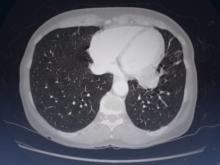

This video presents the case of a 65-year-old woman with a neuroendocrine tumor in her left lower lobe. The tumor invaded the pericardium and was staged as M1a, for which curative resection was not recommended. An initial single port VATS biopsy confirmed the pericardial invasion and obtained the histology. The tumor had a Ki 67 proliferation index of 10-15%, which put it in a moderate degree of malignancy. The tumor was expected to be indolent, and invasion into the pericardium would inevitably lead to the complication of pericardial effusion and possibly heart involvement. At the multidisciplinary meeting, it was suggested that a palliative procedure should be attempted to prevent this complication. In view of the slow rate of tumor growth, it was fully explained to the patient that the surgery would not be curative, but the redo-operative strategy was to inspect and assess the degree of pericardial invasion, and if appropriate, to proceed to lower lobectomy.